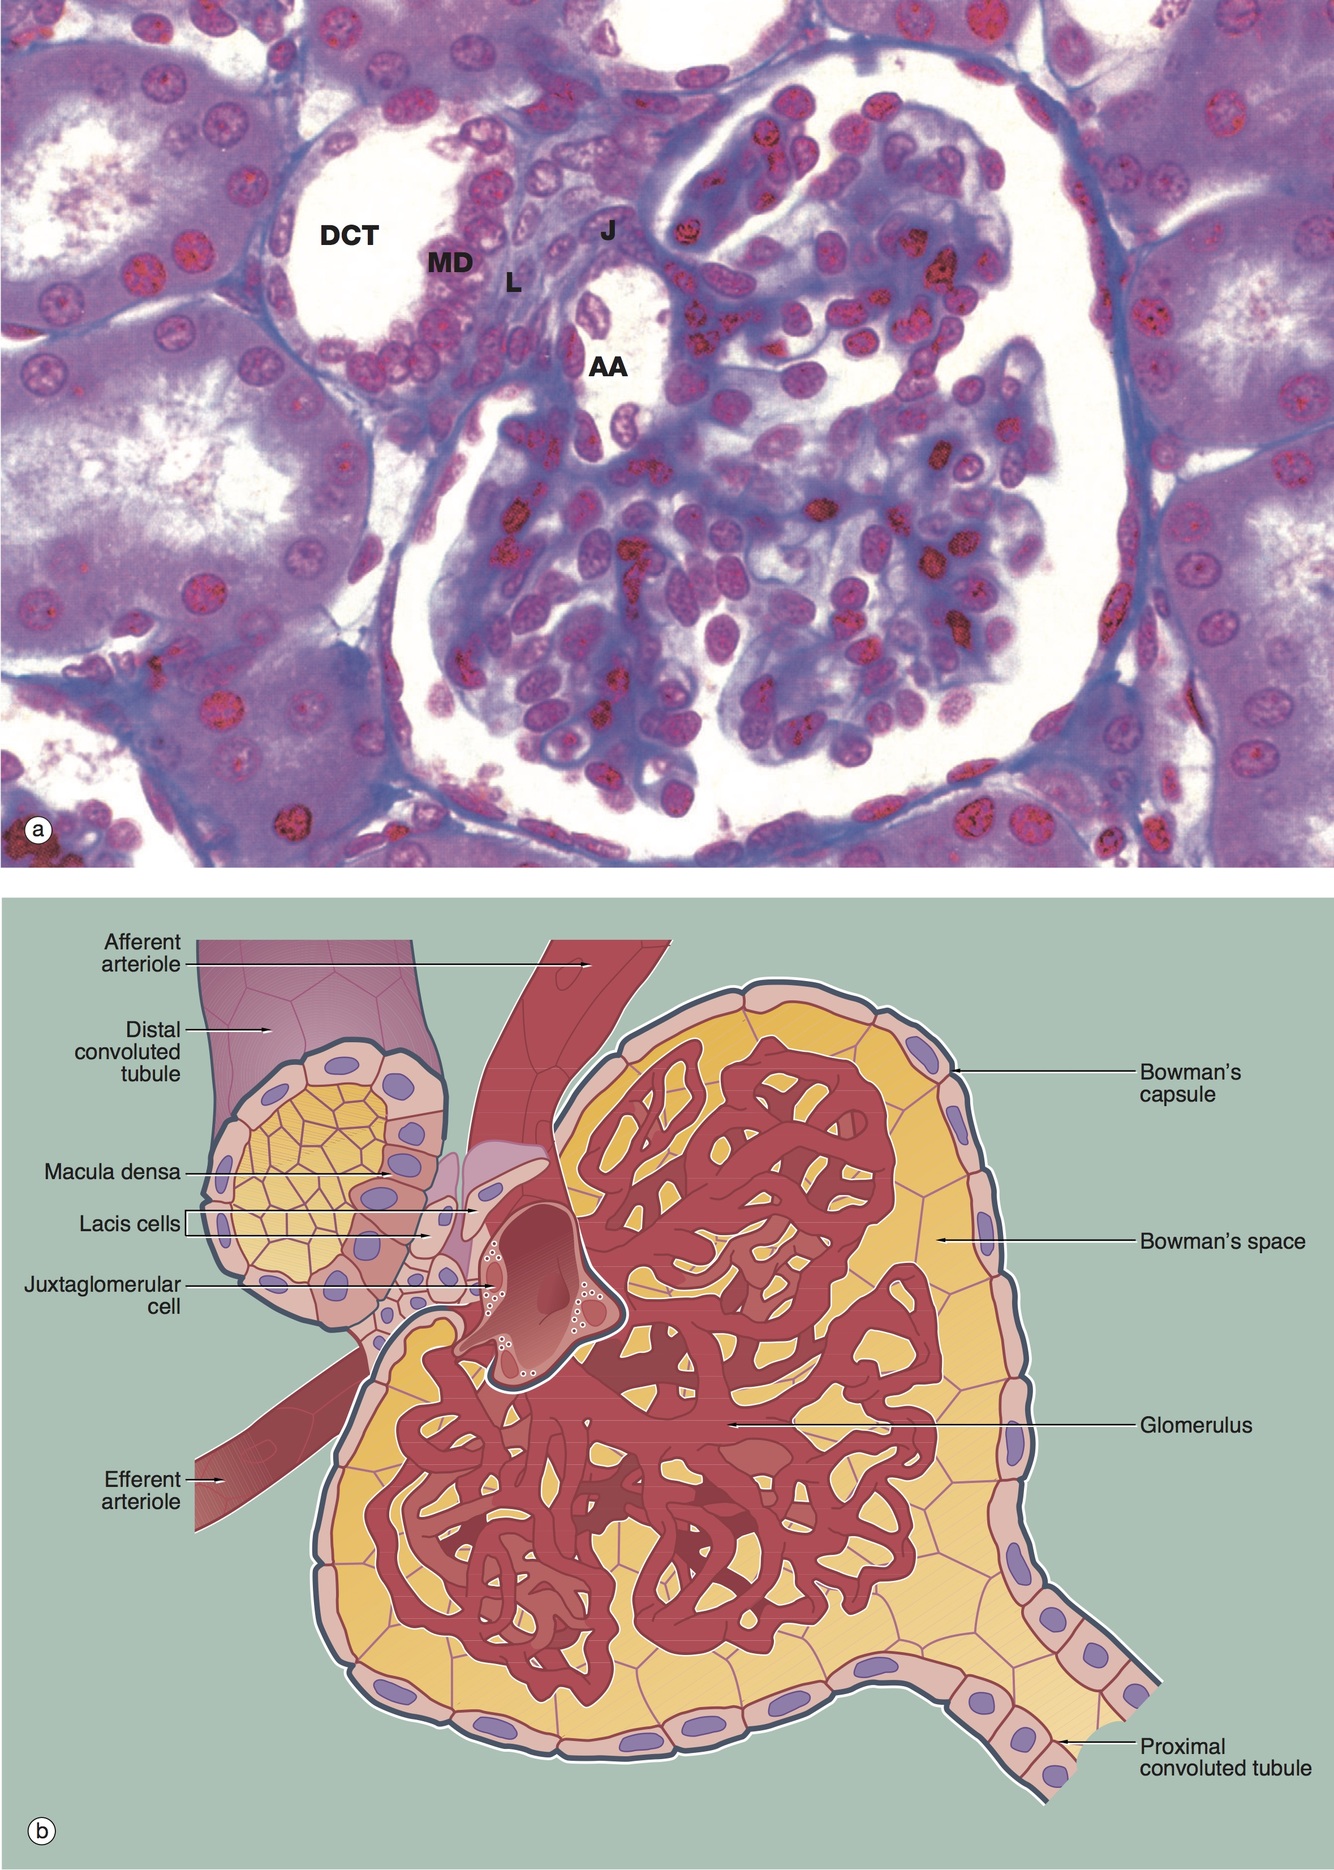

Juxtaglomerular Apparatus

Includes: